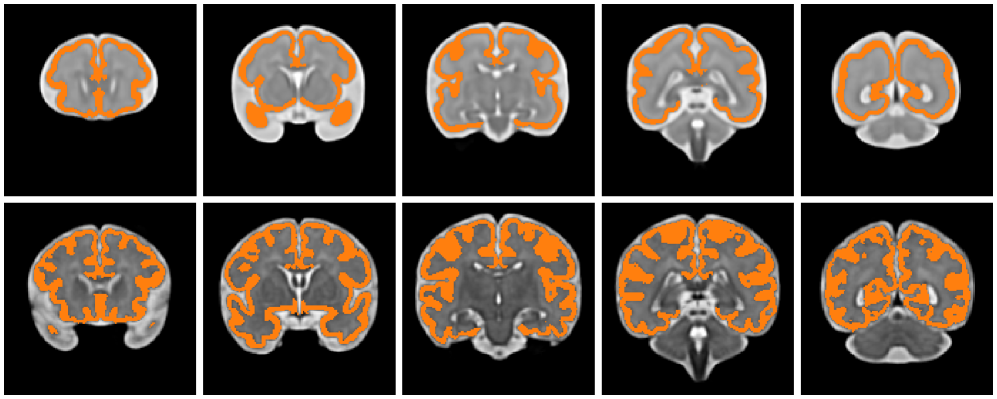

To date, only a few datasets are publicly available [13]. The first one was the Fetal Tissue Annotation and Segmentation Dataset (FeTA) [41, 42], led by the University Children’s Hospital Zürich and the University of Zürich, which gathered 50 manually segmented pathological and non-pathological fetal brain MRIs, across a range of gestational ages (20 to 33 weeks). On the other hand, a number of atlases are found online, such as the Spatiotemporal Atlas (STA) [43]. It contains representations of the average fetal brain, at one-week intervals between 21 and 38 weeks gestational age (Fig. 4). These images were obtained via diffeomorphic deformable registration of 81 T2-weighted MRI scans of healthy fetuses. As opposed to the clinical dataset FeTA, atlas data are smoother and easier to work with, and will be employed in this article.

We observed that most slices fall into one of three types: the cortical plate forms either (i) one circle (first two slices in both rows of Fig. 4), (ii) two disjoint circles (last slice), or (iii) an “open circle”, i.e., a circular arc (third and fourth slices). These cases are identified by inspecting the persistence diagram as follows.

Because the cortical plate is the only class to identify, we expect to only use Module 2 of our method. However, as shown in Fig. 4, it forms a perforated sphere, opened at the level of the cerebellum (third and fourth slice of both rows). Consequently, the homology groups of the cortical plate are all trivial, and it cannot be detected with our method. In order to circumvent this issue, one could modify the image to force the appearance of homology—for instance by “closing” the sphere, as we did with the myocardium in 3D. Instead, we suggest a different strategy: we study the image slice by slice, in the coronal plane.

We found that, averaged over the whole collection of 18 images, 56.95% of the non-empty cortical slices satisfy the hypothesis. In fact, the faulty slices can be divided into two types: either the cortical plate consists of several convex connected components, or it forms an open circle (as observed in the middle slices of Fig. 4). Although not studied further in this work, these slices warrant special attention to improve the scores.